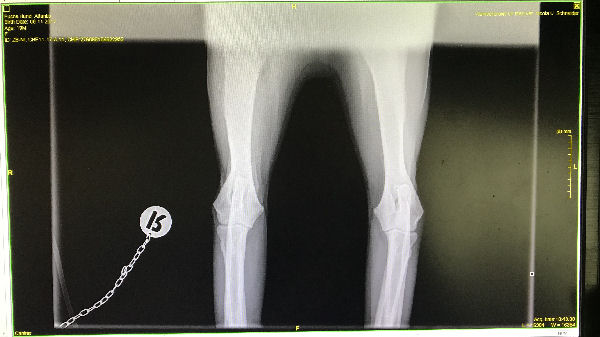

Atlantis - ED-Röntgen

img_5246 (1)-Atlantid-ed-links

img_5247 (1)-Atlantis-ed-rechts